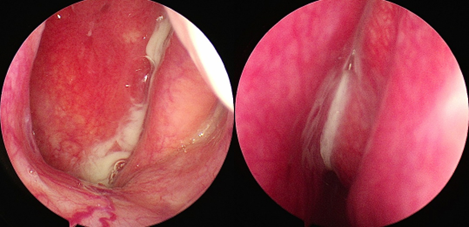

鼻内镜检查单侧中鼻道脓性物(下图)

中鼻道脓性物流向鼻咽部

鼻内镜检查中鼻道可见脓性鼻涕、水肿或息肉

如果内镜检查阴性,但症状或CT符合;